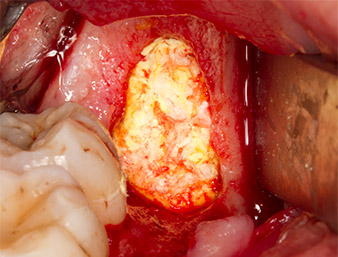

Il tessuto al di sopra del residuo di radice non era completamente ossificato ed era costituito per la maggior parte da tessuto di granulazione modificato dall'infiammazione (Fig. 4).

Per ottenere materiale autogeno per il successivo trattamento della ferita, sono stati estratti frammenti di osso sano nella zona del residuo di radice con uno strumento piezochirurgico (Piezomed B5) (Fig. 5).